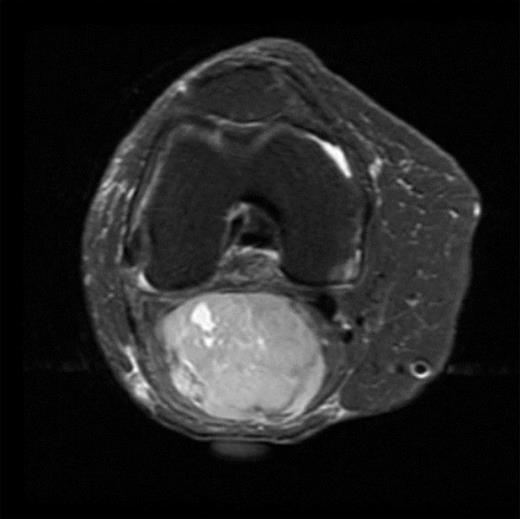

The MRI scan of the right knee (Figs 2 and 3) with gadolinium-enhancement showed a large mass lesion in the posterior aspect of the right knee extending into the popliteal fossa and into the upper third of the right leg having appearance of bursal pathology. Post gadolinium images showed evidence of circumferential rim enhancement but no internal enhancement indicating the presence of a fluid filled lesion. The mass (Figs 4 and 5) measured ∼8.39 × 6.14 × 12.72 cm and was seen between semimembranosus and biceps femoris muscles. There was no evidence of any infiltration of either the sciatic nerve or the popliteal vessels. A likely diagnosis of complicated synovial cyst with a differential diagnosis of haematoma was reported and a provisional diagnosis of Baker's cyst was established.

T1-weighted MRI image showing mass occupying whole of posterior aspect of knee extending to proximal portion of the leg.